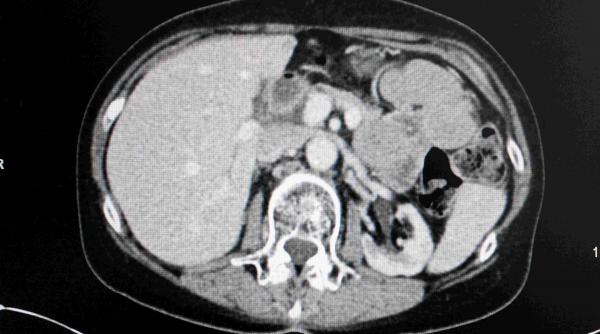

Tomografia computerizată (CT) este un test imagistic medical care a devenit indispensabil și efectuat pe scară largă, pentru diagnosticarea rapidă a unor probleme grave, cum ar fi tumori, AVC-uri, fracturi sau leziuni interne după accidente.

Radiațiile ionizante de la CT sunt cancerigene cunoscute, riscurile de cancer induse de acestea variind în funcție de doza de radiații, care depinde de indicația clinică; regiunea corpului care a fost scanată; sexul, vârsta și dimensiunea pacienților. Estimările anterioare privind aceste riscuri au fost publicate în 2009, însă numărul investigațiilor CT a crescut cu peste 30% de atunci, astfel că oamenii de știință au vrut să vadă ce impact are asupra sănătății publice utilizarea actuală a acestor scanări și să identifice tipurile de examinare cu cel mai mare risc, grupele de vârstă și sex.